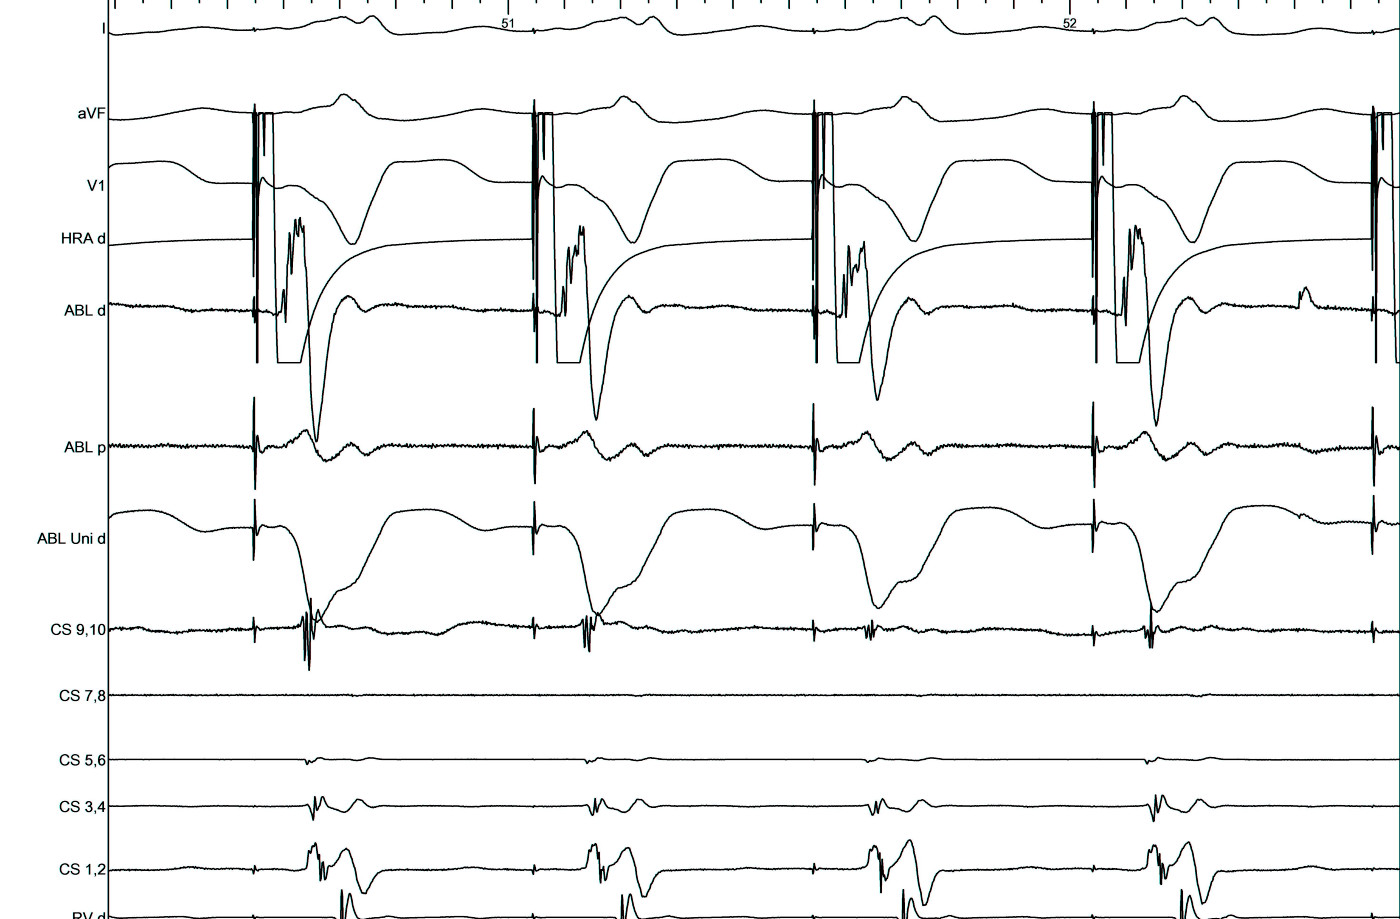

Unipolar EGM

unipolar.jpg

good_signal_llap_antegrade.png